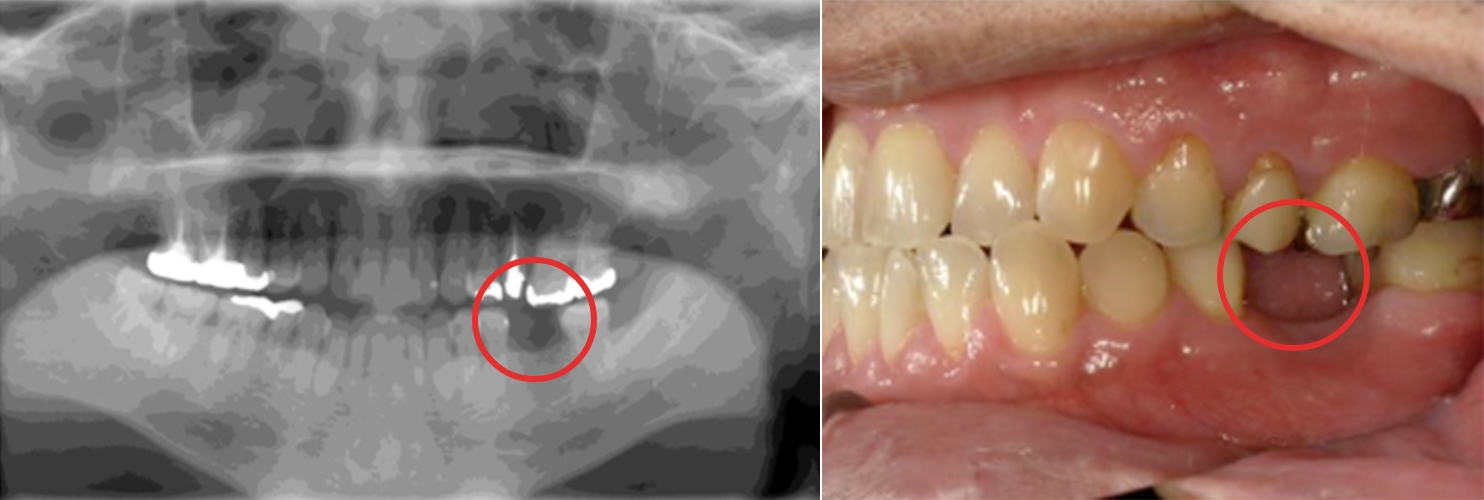

Dさん

インプラントが折れてしまった方

5年前、右側に入れたインプラントが折れてしまいました。他院で受けた治療でしたが、川越歯科医院へ相談に行きました。

治療概要

| ご希望 | 他院で受けた手術だったけれど、川越歯科医院で再度インプラントを入れ直してほしい。左側もうまく咬めないので、これを機にインプラントにしたい。 |

|---|---|

| 治療内容 | 右側のインプラントを撤去し同時に埋入。完治後に左側もインプラントにしたいとの要望を受け、抜歯とともに埋入。 |

| 治療期間・回数 | 3〜5ヶ月・4〜6回 |

| 費用 | 40万円 〜 44万円 |

| 想定されるリスクと副作用 | インプラントとGBR(歯槽骨を再生する治療)を同時に行うと痛みが1~2週間続く、腫れ、内出血 |

手術を終えて

楽に治療を受けたかったので、静脈内鎮静法の効果で半分寝た状態で治療を受けることができました。実は、インプラントが一度折れてしまったので今回もインプラントするかを迷っていました。

先生から一言

インプラントの撤去と埋入を同時に行い、手術回数が少なく済むようにしました。できるだけ手術回数を減らしたい、怖い思いをしたくないなど、小さなご要望でもなんでもお話しください。できる限り叶えられるよう、最善を尽くした治療を行います。